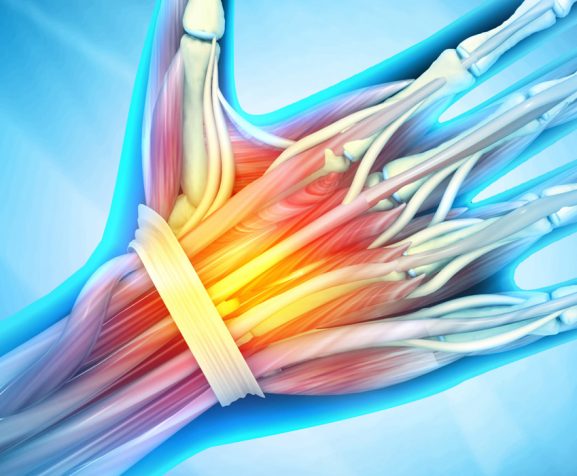

Arthritis

Degenerative Disc Disease

Herniated Discs

Spinal Stenosis